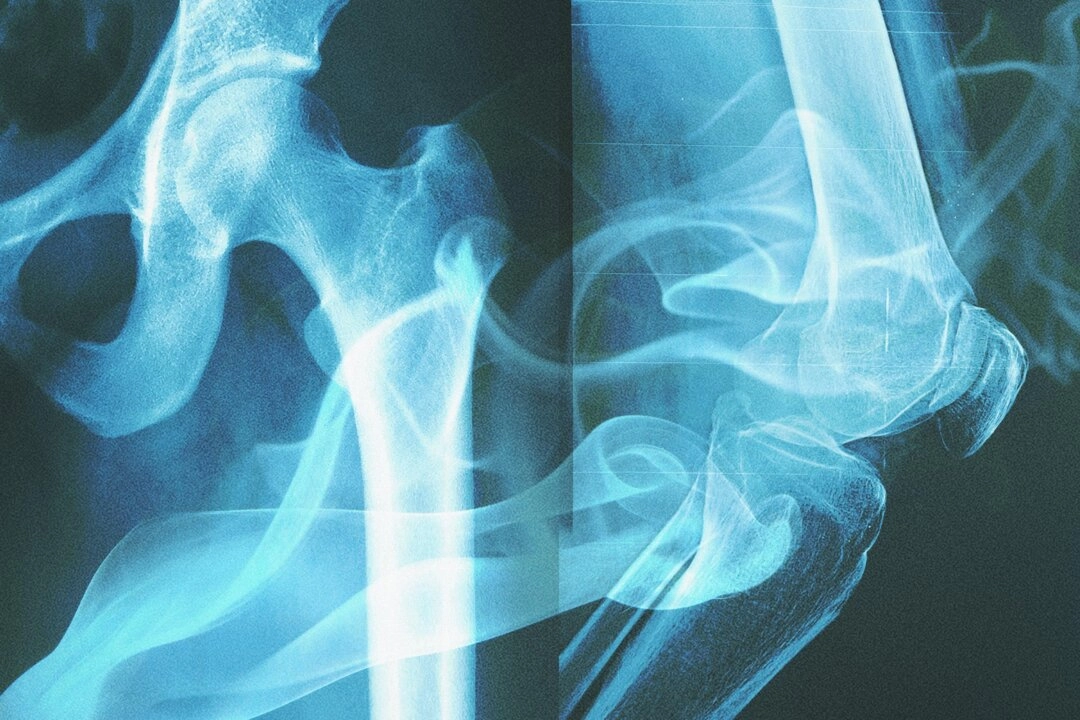

Výskumný tím odobral zo stehennej kosti (femuru) každej osoby približne 40 miligramov kortikálneho tkaniva (čo je približne hmotnosť zrnka ryže) a analyzoval ju pomocou kvapalinovej chromatografie a vysokorozlišovacej hmotnostnej spektrometrie – techniky, ktorá oddeľuje a presne identifikuje chemické zlúčeniny vo vzorke na základe ich hmotnosti a štruktúry.

Kosť nie je statické tkanivo – počas života sa neustále pretvára. Metabolické informácie z kostných buniek sa ukladajú v kostnej štruktúre. Keď človek fajčí, chemické látky sa dostávajú do krvného obehu a ovplyvňujú metabolizmus v celom tele vrátane kostných buniek. Tieto metabolické zmeny vytvárajú „chemické fosílie“, ktoré sa trvalo zaznamenávajú v kostiach.

Štúdia sa zamerala na kortikálnu kosť, hustú vonkajšiu vrstvu kostného tkaniva, ktorá je menej citlivá na vonkajšie vplyvy prostredia. Aj keď povrch kosti zmení farbu v dôsledku zloženia pôdy alebo vlhkosti, jej vnútorná chemická signatúra zostáva nezmenená.

Hoci táto štúdia neskúmala priamo ochorenia, moderná medicína jasne potvrdzuje škodlivé účinky tabaku na zdravie všetkých kostí. Fajčenie znižuje hustotu kostí, urýchľuje rozvoj osteoporózy, zvyšuje riziko zlomenín a spomaľuje ich hojenie po úrazoch. Zvyšuje tiež riziko paradentózy, závažného ochorenia ďasien, ktoré môže viesť k úbytku kostnej hmoty v čeľusti.